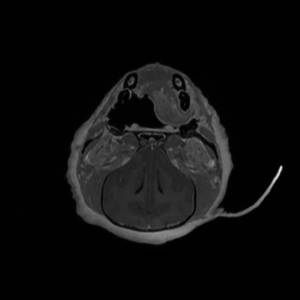

Main Gallery

Playing with a photo gallery function. It is possible to have multiple galleries, each within a namespace.